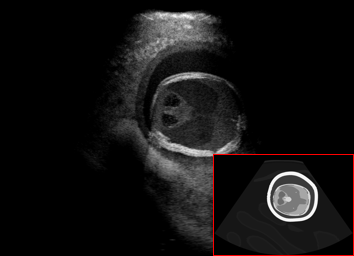

Real in-vivo images. 22 ultrasound sequences were collected using a GE Voluson E8 machine during standard fetal screening exams of 8 patients. Each sequence is several seconds long. We extracted all 4427 frames and resize them to , see Fig. 2 for some examples. The resulting image set was randomly split into training-validation-test sets by a 80-10-10% ratio.

US simulation. We used a ray-tracing framework to render B-mode images from a geometric fetal model, by simulating a convex probe placed at multiple locations and orientations on the abdominal surface, with imaging settings listed in Tab 1. At each location, simply rasterizing a cross-section through the triangulated anatomical surfaces at the ultrasound center imaging plane provided corresponding semantic maps. Fig. 3 shows example B-mode images with corresponding semantic maps. A total of simulated frames were resized to and randomly split into training-validation-test sets by 80-10-10%.